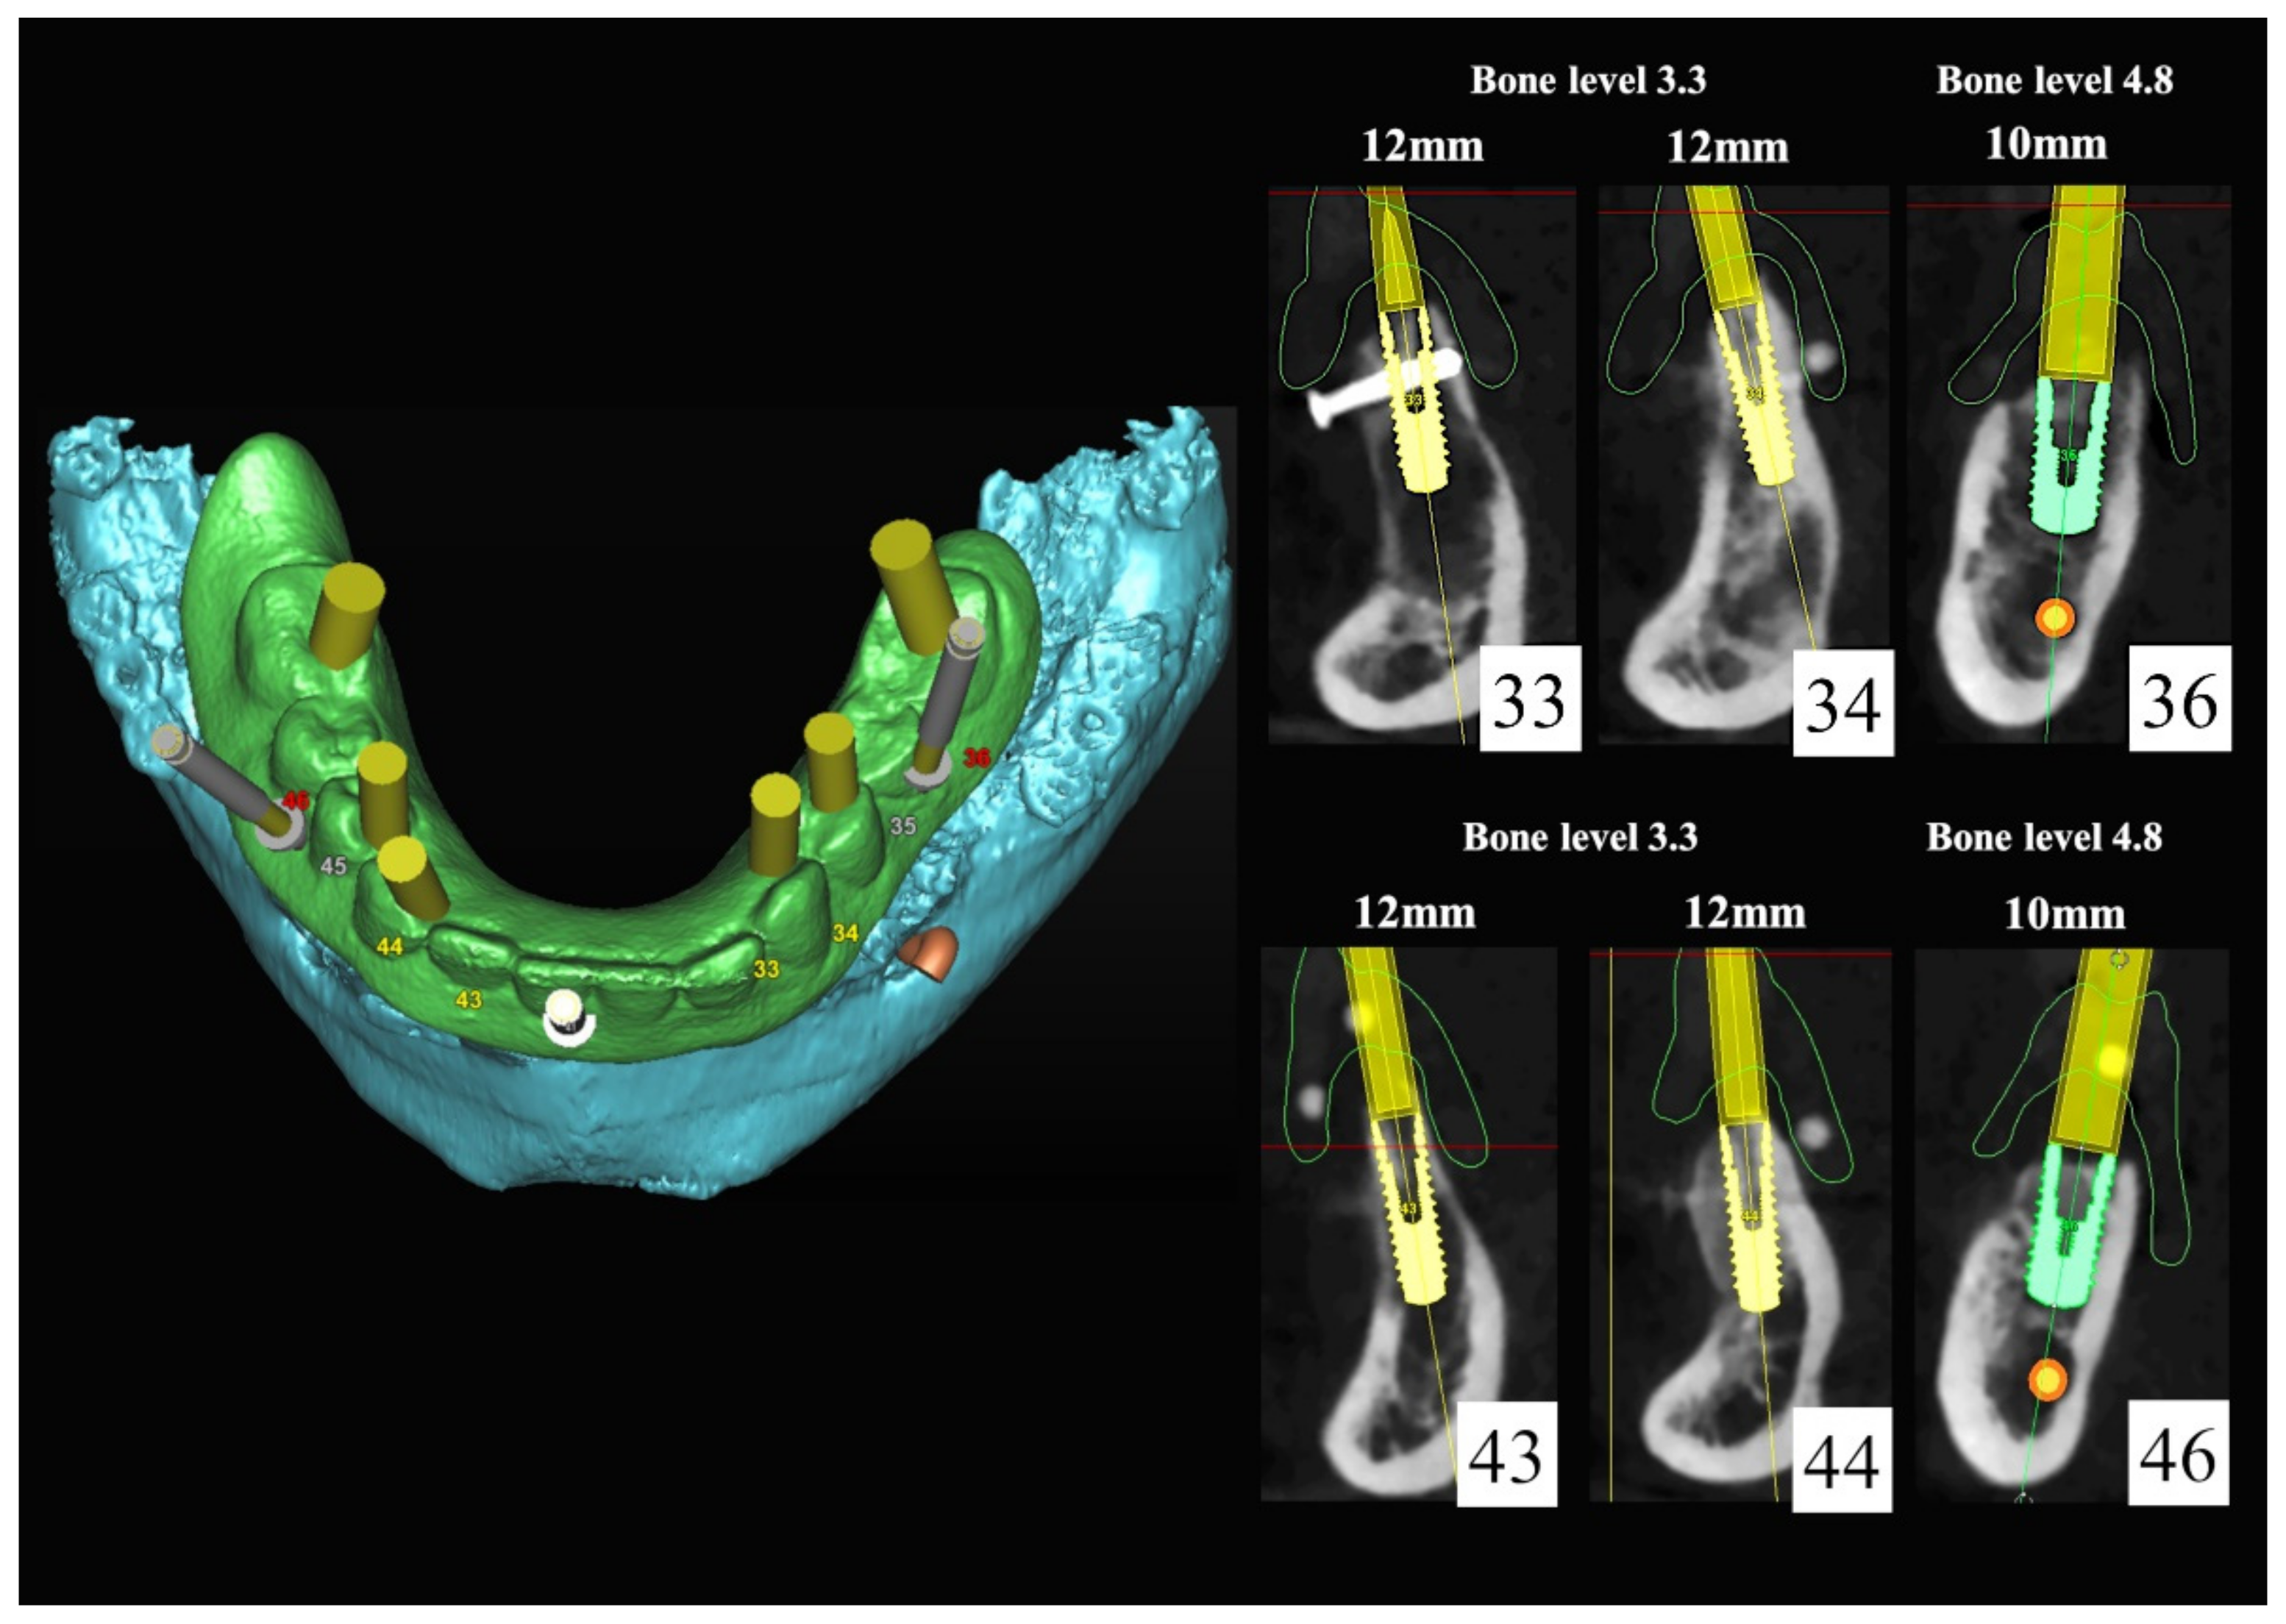

6.3.1. Complete Mandibular Edentulism (Mandibular Bar-Retained Implant-Supported Overdenture Using Straumann Pro Arch® Protocol)

6.3.2. Preoperative Documentation:

6.3.3. Image Segmentation and Virtual Planning: